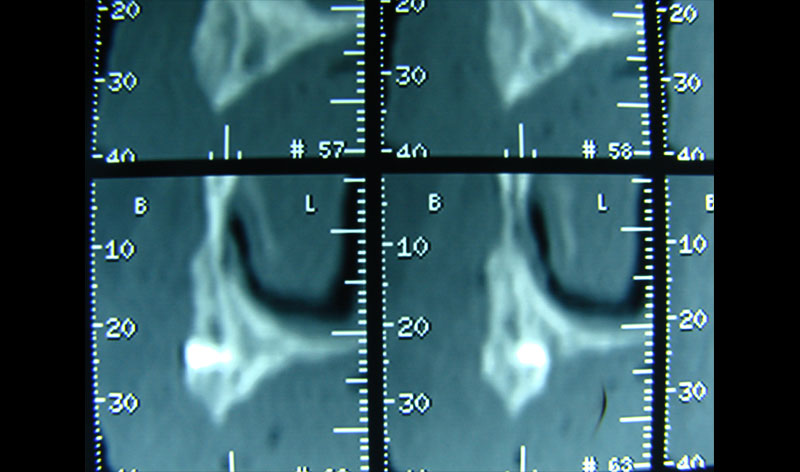

Existen muchas situaciones donde la pérdida y la atrofia ósea son tan graves que nos obligan a recurrir a la cresta iliaca del paciente, para conseguir el volumen óseo necesario para la correcta reconstrucción del maxilar. Así, la colocación de implantes será posible a los 3 meses.